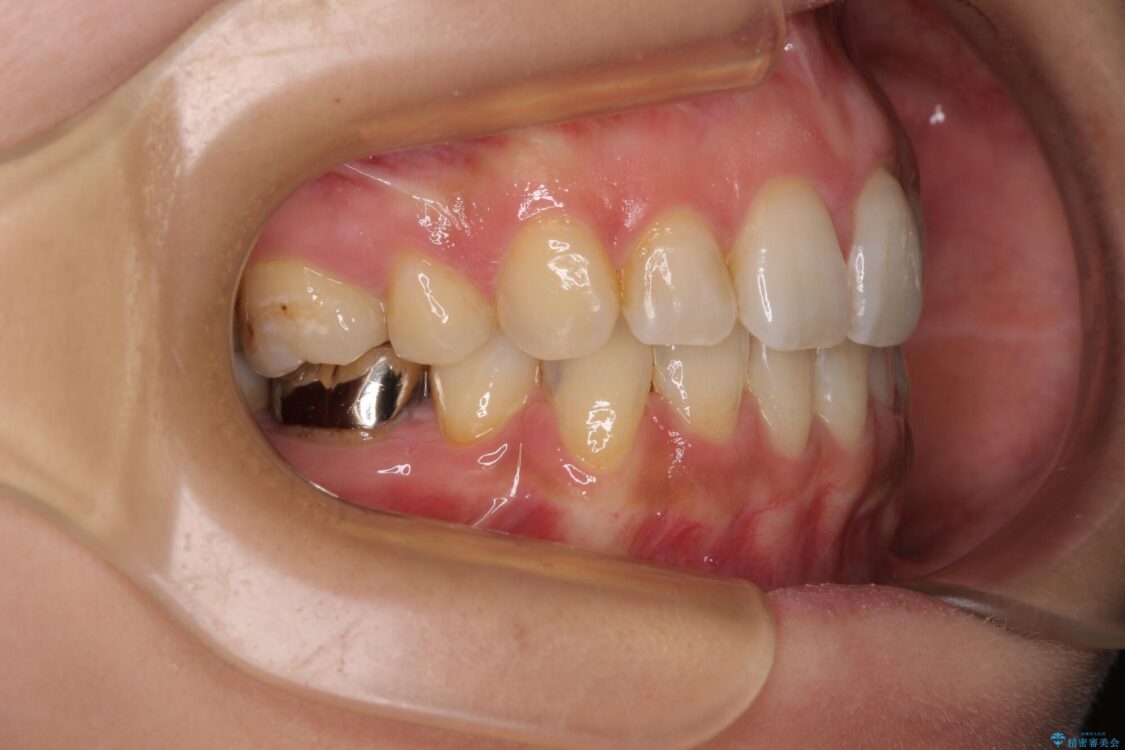

前歯のデコボコと上顎の前突感による口の閉じにくさを気にして来院された患者様です。

目立たない装置を希望されたので、上顎が裏側装置のハーフリンガルを選択し、上下左右の小臼歯(計4歯)を抜歯して矯正治療を行うこととしました。

治療前

• デコボコと口元の突出感 ハーフリンガルでの抜歯矯正 治療前画像